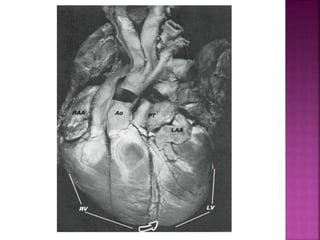

Right ventricle –Hypertrophied,Sub aortic conus Left ventricle- Normal to thinned out, Pulmonary-Mitral continuity Aorta- Anterior and right of PA Atria – Normal (RA>LA) Atrio-Ventricular valves – Same level Conduction tissue – Normal position and abnormal shape

Right ventricle –Hypertrophied, Sub aortic conus

Left ventricle- Normal to thinned out, Pulmonary-Mitral continuity

Aorta- Anterior and right of PA

Atria – Normal (RA>LA)

Atrio-Ventricular valves – Same level

Conduction tissue – Normal position and abnormal shape

Normal -2/3 and Abnormal -1/3